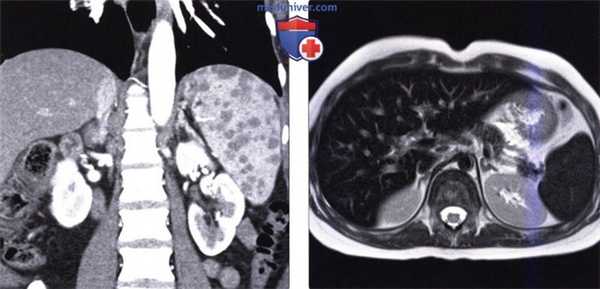

(Справа) На аксиальной КТ с контрастным усилением визуализируется «объемное образование» в хвосте поджелудочной железы, имеющее одинаковую плотность с селезенкой (добавочная селезенка), которое можно ошибочно принять за первичную (например, нейроэндокринную) опухоль поджелудочной железы. Медиальная поверхность селезенки, а также аксиальные срезы на трех различных уровнях. Селезенка может иметь различный размер и форму даже у одного и того же человека в зависимости от гидратации и питания. С медиальной стороны селезенки часто имеется участок, выбухающий в промежуток между желудком и почкой. Селезеночная артерия и вена, располагающиеся в селезеночно-почечной связке, проходят параллельно телу поджелудочной железы. Хвост поджелудочной железы также проникает в ворота селезенки через селезеночно-почечную связку. В желудочно-селезеночной связке находятся короткие артерии желудка и левая желудочно-сальниковая артерия, кровоснабжающие желудок и верхнюю часть селезенки.

(Слева) На корональной КТ с контрастным усилением определяется умеренно выраженное увеличение селезенки с наличием множественных гиподенсных узлов в ее паренхиме. Позднее у этого же пациента была выявлена внутригрудная лимфаденопатия; при биопсии селезенки подтвердился саркоидоз.

(Справа) На аксиальной Т2 ВИ МР томограмме определяется выраженное снижение интенсивности сигнала от печени, селезенки и костного мозга у пациента с гемосидерозом, обусловленным множественными переливаниями крови.